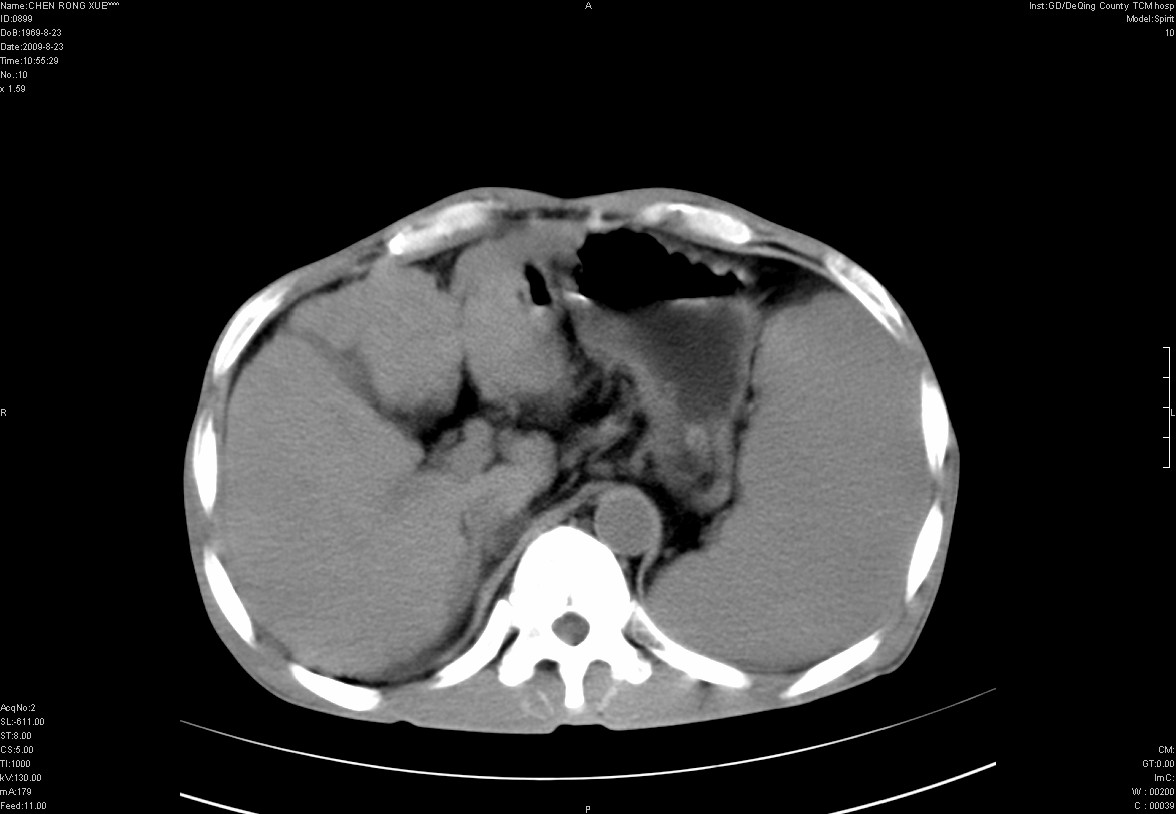

以下是引用zxl51642在2009-8-23 12:56:00的发言:[br]1、肝硬化、脾大;2、慢性胆囊炎;3、右肾占位并右侧腰大肌受侵,考虑恶性可能性大,建议增强扫描进一步检查。

以下是引用qiuleiyu在2009-8-23 15:17:00的发言:[br]1、慢性肝病,肝硬化,脾大,门脉高压。胆囊小结石。[br]2、右肾明显肿大,伴片状低密度灶,累及右侧腰大肌,肿瘤及炎症性病变皆有可能大,建议增强。

以下是引用zjzjr在2009-8-23 17:42:00的发言:[br]1、慢性肝病,肝硬化,脾大,门脉高压。胆囊小结石。[br]右肾脓肿波及肾周,建议增强

以下是引用dyqct在2009-8-23 16:53:00的发言:[br][quote]以下是引用qiuleiyu在2009-8-23 15:17:00的发言:[br]1、慢性肝病,肝硬化,脾大,门脉高压。胆囊小结石。[br]2、右肾明显肿大,伴片状低密度灶,累及右侧腰大肌,炎症性病变可能,建议增强。